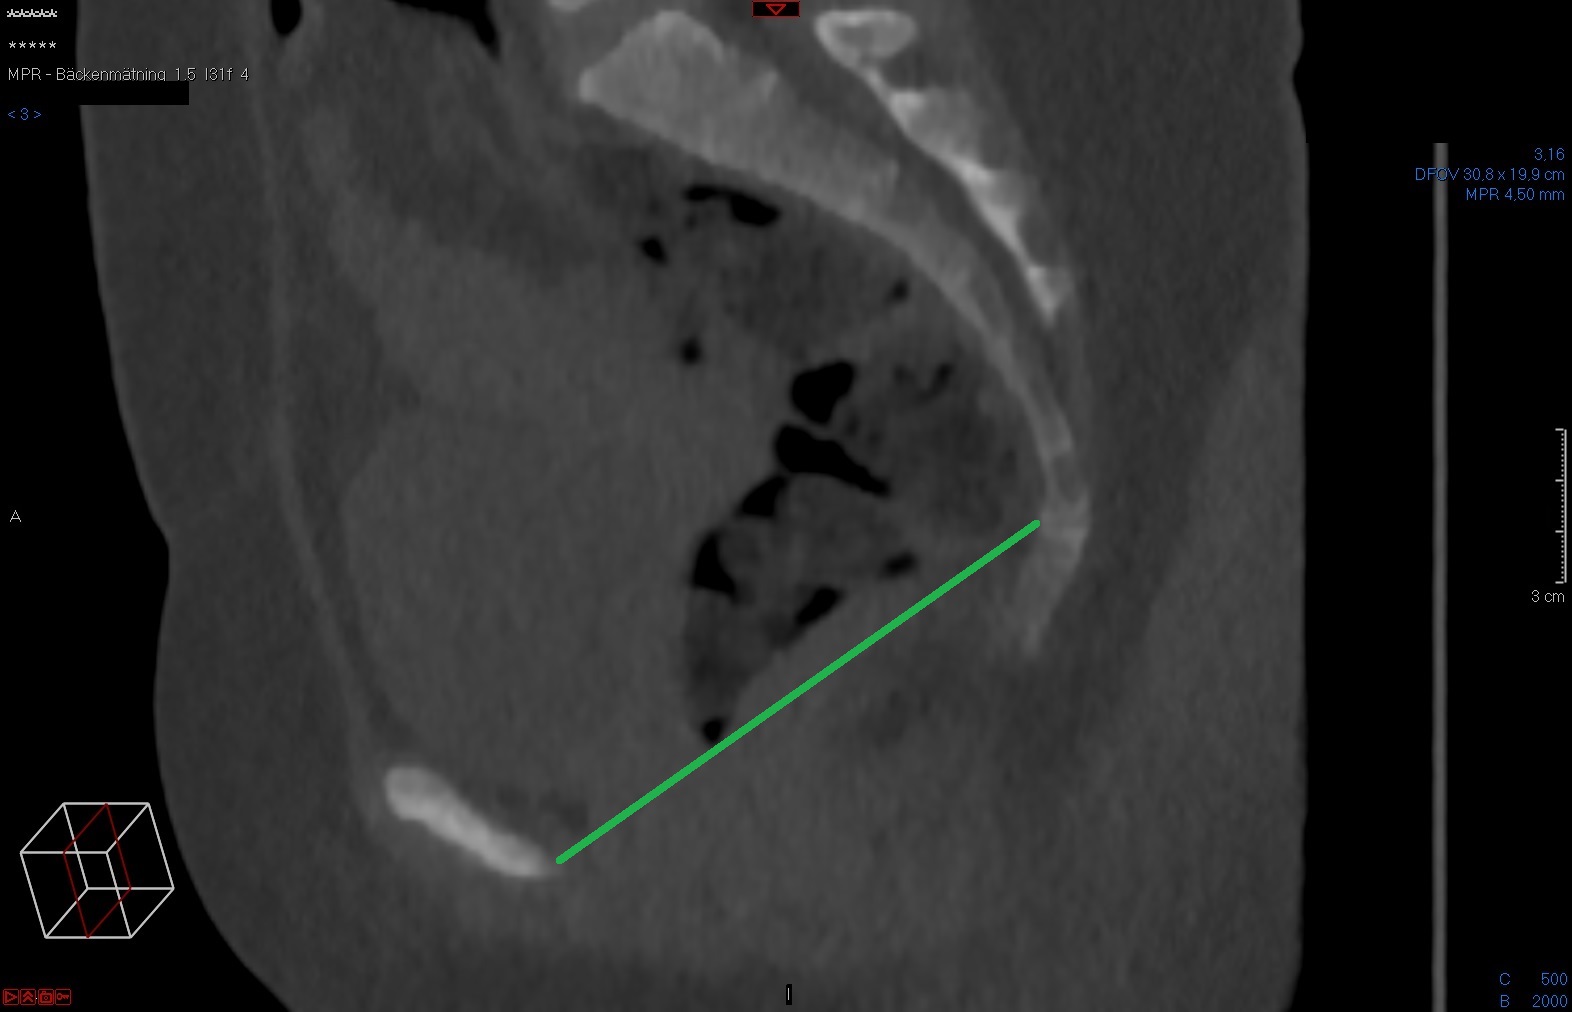

Tunna snitt-serien sagittalt i Power Viewern ("MPR"), snittjocklek 7-10 mm, skelettfönster. Scrolla fram till symfysens mitt. Mät det kortaste avståndet mellan symfysens kraniala-dorsala omfång och sacrums kraniala-ventrala omfång.